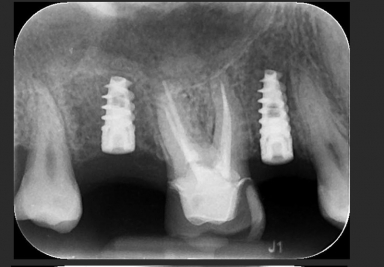

Dental implants premolar

Dental implants upper second premolar, upper second molar